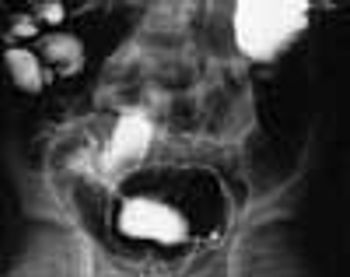

A 6-year-old boy presented with bloody diarrhea; fatigue; decreased appetite; weight loss; and occasional, mild abdominal pain for the past 2 months. The child had 6 to 8 bowel movements daily, 1 or 2 of which occurred at night.

A 6-year-old boy is brought for evaluation of bloody diarrhea, fatigue, decreased appetite, weight loss, and occasional, mild abdominal pain of 2 months' duration. The child had 6 to 8 bowel movements daily, 1 or 2 of which occurred at night.